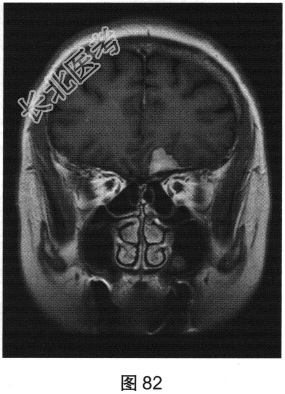

- 多项选择题2.[提示]患者行MRI检查,如图80~图85所示。患者MRI检查的阳性影像学表现包括( )

A、MRI示右侧大片水肿

B、病变增强扫描未见明显强化

C、MRI示左侧大片水肿

D、FLAIR呈稍高信号

E、病变增强扫描可见明显强化

F、FLAIR呈稍低信号

G、MRI示左侧异常信号影

H、MRI示右侧异常信号影